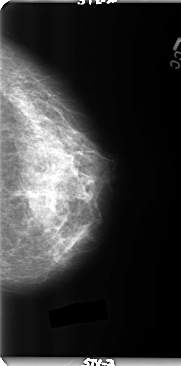

B_3156_1.LEFT_CC

LEFT_CC LINES 4752 PIXELS_PER_LINE 2352 BITS_PER_PIXEL 12 RESOLUTION 50 NON_OVERLAY